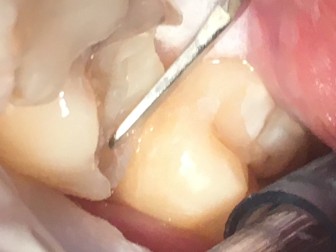

Se aplica CARIESEND y repite el proceso hasta

lograr una cavidad limpia

Se prepara la superficie

con desmineralizante

Despues de enjuagar, se aplica la resina en capas

Después de cada capa

de resina se polimeriza

con lampara de fotocurado

Utilizamos composite condensable de baja contracción en posteriores

Con un buen registro de oclusión, se inicia el pulido

y acabado final.

El resultado final de la restauración en posteriores con la morfologia y oclusión ideal.